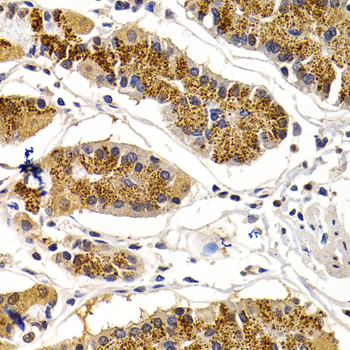

Immunohistochemistry of paraffin-embedded human normal colon using CDK7 antibody at dilution of 1:200 (400x lens).